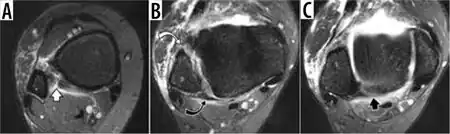

| MRI showing a syndesmotic injury in a high ankle sprain | |

Those who sustain high ankle sprains usually present with pain in the outside-front of the leg above the ankle, with increased discomfort when twisting (external rotation) is applied. In some cases, the diagnosis is only made after treatment for the more common, lateral, ankle sprain fails.[3] Diagnosis may also be delayed because swelling is usually minor or nonexistent and the true nature of the injury unappreciated.[4] A variety of diagnostic tests have been described such as the 'squeeze' (compressing the tibia and fibula above the midpoint of the calf), 'dorsiflexion with compression' (patient dorsiflexes the foot while the examiner compresses the internal and external malleolus), and 'external rotation' (patient sits with leg dangling and ankle at 90° and external rotation then applied to the foot) etc. None of them performs sufficiently well to allow diagnosis to be made on the basis of a single test,[5] and is usually made by combining multiple tests supplemented with appropriate imaging when indicated. Plain radiographs, Ultrasound[6] or MRI may be used for diagnosis.

In the case of X-rays, demonstration of widening of the tibia and fibula 'mortise', a fracture of the medial malleolus, or a Maisonneuve fracture, will indicate an unstable or potentially unstable injury. However, 'normal' x-rays do not exclude significant ligament injury, and in one study, the ratio of diagnostic X-ray to known syndesmotic injury was only one in 17. By contrast, ultrasound may permit the injury to be visualized while the mortise is being stressed.[6] Consequently, a diagnostic modality such as ultrasound or magnetic resonance imaging (MRI)[5] that demonstrates the ligament itself may be helpful, if clinical suspicion remains.[7]